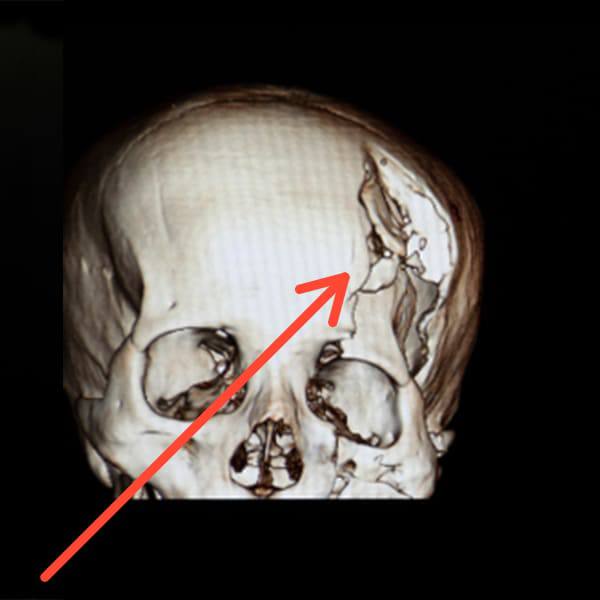

Franeli, descrito como un muchacho, ahora deberá enfrentar las consecuencias permanentes de este trauma craneal. Su condición ha provocado tristeza e indignación en la comunidad, donde numerosas voces se han levantado con llamados a que se haga justicia, al tiempo que se pide por su pronta recuperación y bienestar.

El hecho ocurrió en horas de la mañana del sábado. El audiovisual captado muestra con claridad el desarrollo del incidente: en primer lugar, los vehículos se detienen en plena vía, mientras Franeli busca un objeto en el asiento de su motocicleta. Acto seguido, Braulio desciende portando un bate, ambos se aproximan y discuten. En ese momento, Braulio propina el golpe directo a la cabeza de Polanco.

Tras el impacto, el joven queda tendido e inconsciente sobre el pavimento, situación que obligó a que varias personas en el lugar acudieran rápidamente a socorrerlo. Estas imágenes han circulado en la localidad y han reforzado el sentimiento de conmoción entre los residentes, quienes han mostrado su preocupación por la situación de Franeli.